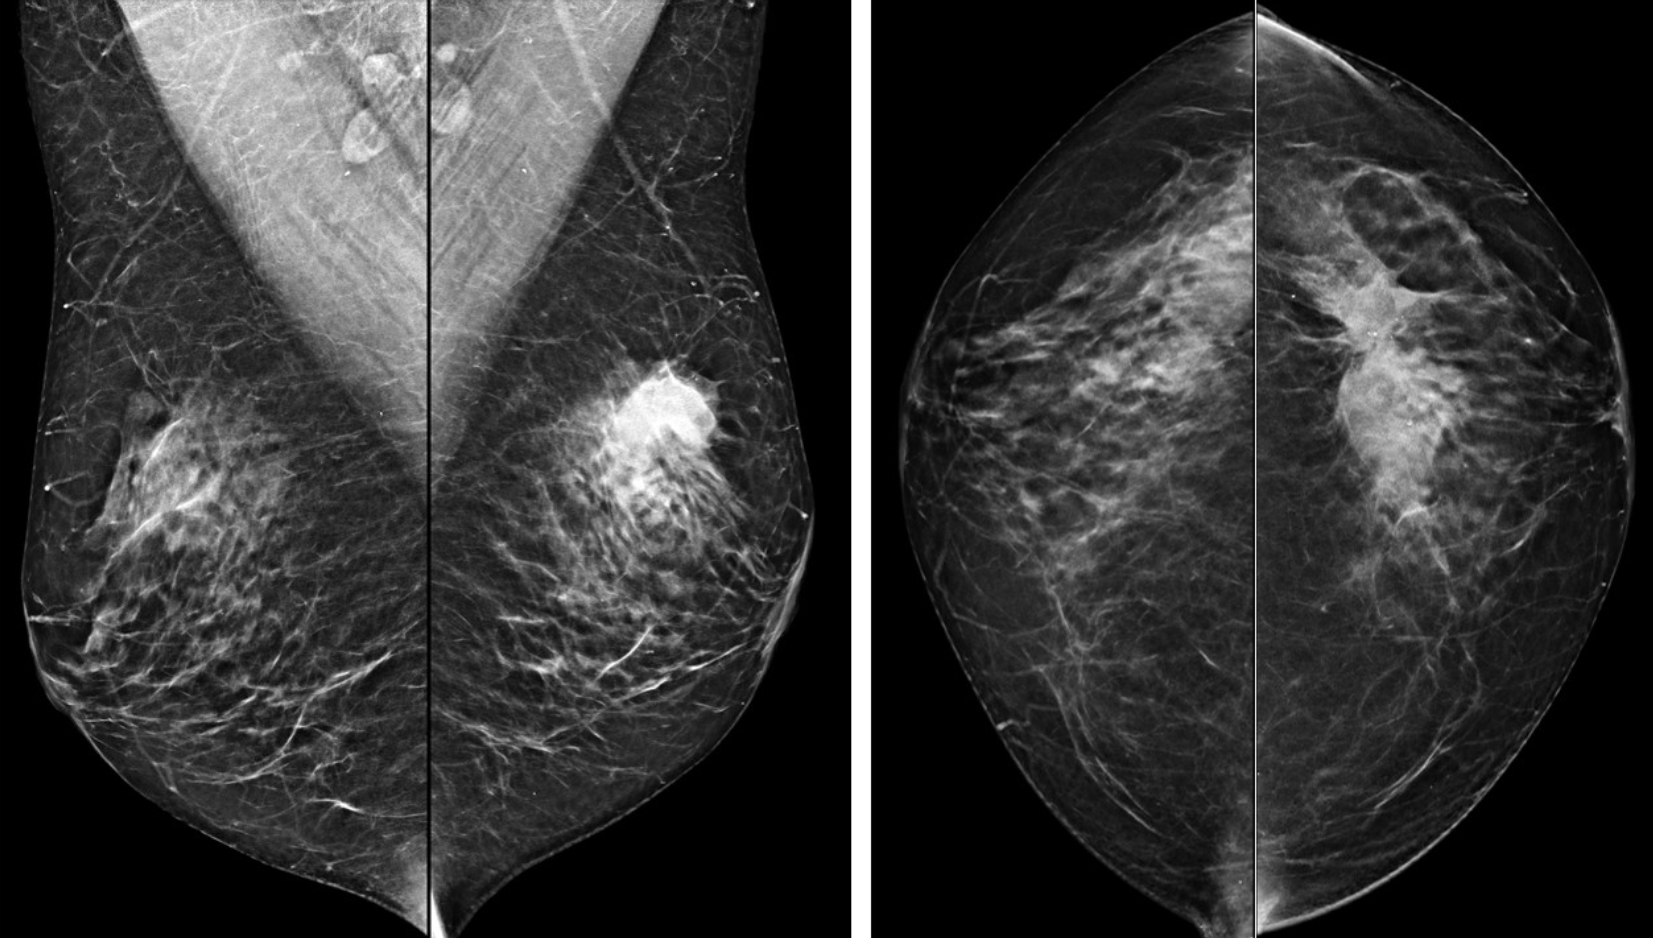

Estudio mamográfico de ambas mamas.

HALLAZGOS RADIOLÓGICOS